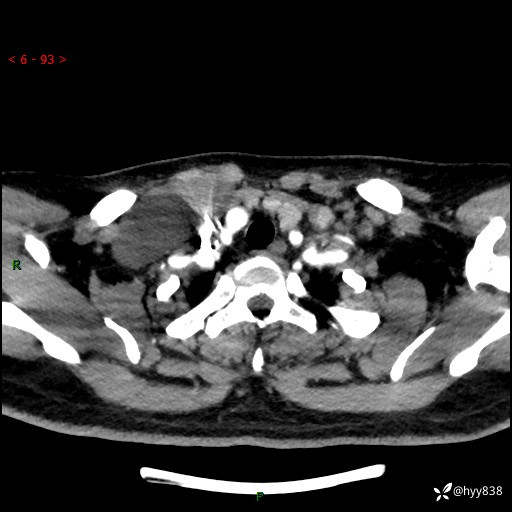

辅助检查:CT

颈部CT平扫

增强动脉期+静脉期